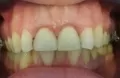

Мне 26 лет, с детства волновал вопрос кривых зубов. Зубы очень слабые и постоянно подвергаются заболеванию кариесом, в следствии чего, почти каждый зуб с пломбой.

Возможно ли выровнять такие зубы, если зуб, который во втором ряду, и передний правый резец мёртвые? Фото прилагаю. И если да, то не повредятся ли, и не отпадут ли пломбы при установке и в процессе выравнивания?